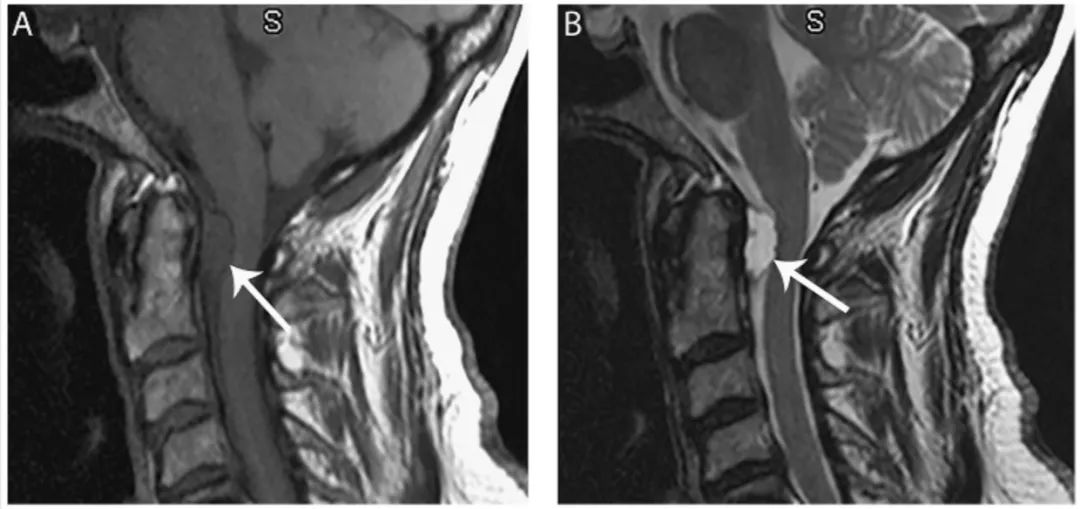

图12 神经管原肠囊肿

颈椎矢状位T1WI(A)和T2WI(B)显示位于颈髓前、颈髓髓连接处下方的局限性囊肿(箭头),脊髓轻微后移。T1WI上囊肿相对CSF呈等高信号,T2WI像为高信号。